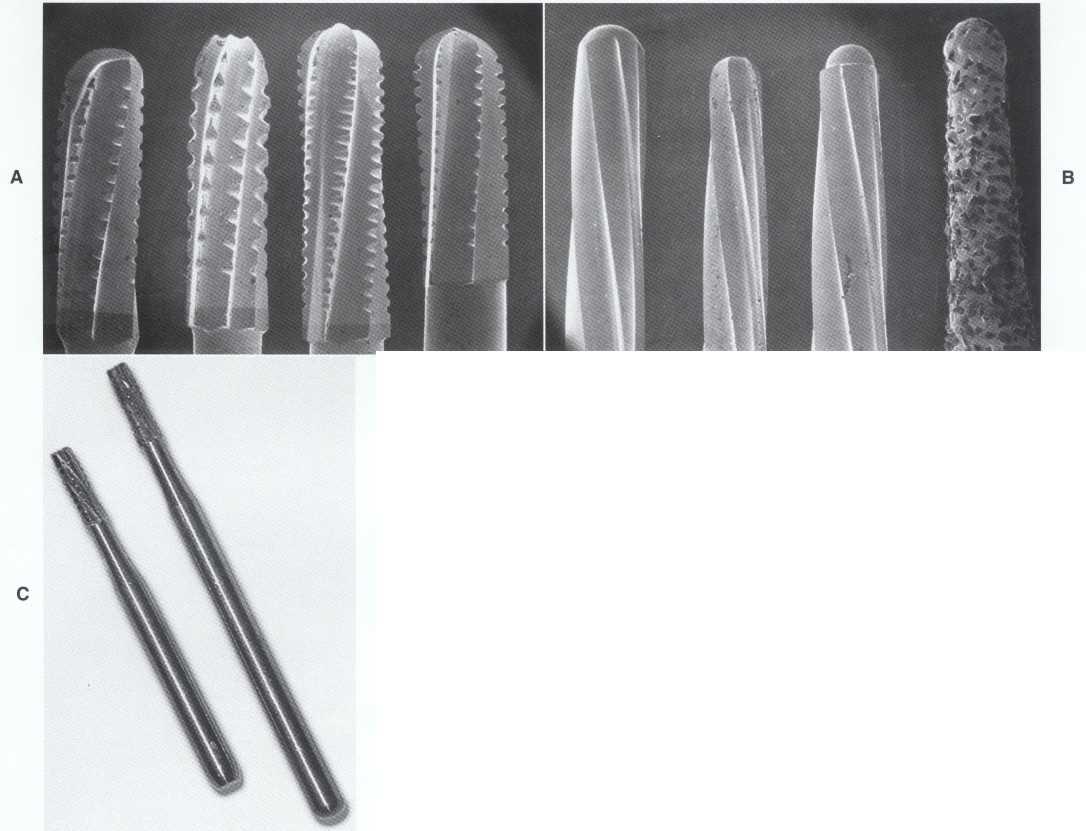

in an uncrowned tooth exhibiting a patent canal, initial access is best accomplished by round or fissure carbide burs (Figure 2-1). Fissure burs such as the #558 produce less "chatter" when penetrating intact enamel or dentin

FIGURE 2-1 From left to right, a #558 surgical length fissure bur followed by #1, #2, #4, #6, and #8 surgical length carbides.These are primarily used for cutting through natural tooth structure.

compared with round carbide burs. In contrast, round carbide burs such as the #6 or #8 seem to be more controllable during the removal of carious dentin.

Round Diamond Burs

New round diamond burs in #4 and #6 sizes work predictably and quickly to cut through both porcelainfused-to-metal (PFM) crowns and the new all-porcelain crowns (Figure 2-2). The clinician should use relatively new diamonds with abundant water and intermittent light pressure to avoid generating excessive heat. If dull diamonds are used, especially without water coolant, the clinician may be tempted to apply excessive pressure to accelerate the cutting process and thereby overheat the crown. This can result in craze lines and fractures, which may chip off during instrumentation (when they are easy to repair) or after treatment completion (when they are not). After removing the porcelain layer of the PFM, the clinician can then use a carbide fissure bur or specially designed metal cutting bur to perforate the metal substructure and underlying foundation.

Tapered Diamonds

Flame-shaped and round-ended tapered crown-preparation style diamonds are excellent for endodontic access (Figure 2-3). They are unequaled for cutting with

FIGURE 2-2 From left to right, round diamonds in sizes #4, #6, #8, and #10. Used with copious water and a very light touch, they can predictably and effortlessly cut through PFM and all-porcelain crowns without fracture.

FIGURE 2-3 Coarse grit flame-shaped diamonds and a few sizes of tapered round-ended diamonds can work wonders for refining access outlines and blending canal orifices. These diamonds can safely cut natural and decayed tooth structure, precious and nonprecious crowns, PFM crowns, and all-porcelain crowns.

control, predictability, and ease; this is one reason they are used for the most delicate crown preparations. Perhaps their use should not be restricted to providing restorative treatment. Crown-preparation style diamonds seem to come in more sizes and shapes than any other bur.

After the initial penetration into the pulp chamber has been accomplished, many clinicians advise using a round carbide to finish unroofing the chamber. Although this technique may work in some cases, it is very difficult to perform, especially on a tooth with a small access. The result of this technique is often an overprepared, uneven, gouged wall that catches the tips of files and hampers the placement of files. A much better and safer option is to use an appropriately sized tapered diamond to open and flare the access. The long cutting surface of the diamond can simultaneously open the cavosurface of the access and smooth irregularities in the access walls. The tip removes the last tags and remnants of the chamber roof and blends the dentin from the cavosurface to the canal orifice.

Penetrators and Metal Cutters

Metal cutting burs are highly practical adjuncts for use with full nonprecious castings and nonprecious sub-

structures of PFM crowns (Figure 2-4). The additional expense of using one or two new penetrating burs as opposed to numerous regular carbide fissure burs is offset by the time savings and reduced frustration. Because of the difficulty in cutting through many restorative materials, especially nonprecious materials, the clinician is often tempted to shortchange the access preparation. Having an arsenal of sharp, new burs specially designed to penetrate these materials helps keep frustration to a minimum.

Surgical Length Burs

Surgical length burs permit displacement of the handpiece away from the incisal or occlusal surface of the tooth, greatly increasing visibility of the cutting tip of the instrument (see Figures 2-1 and 2-4, C). With technical skill, practice, and patience, the clinician can use surgical length burs to gain access in the majority of teeth, including maxillary second molars. Surgical length burs are often useful in teeth that present the greatest problems with access and visibility.